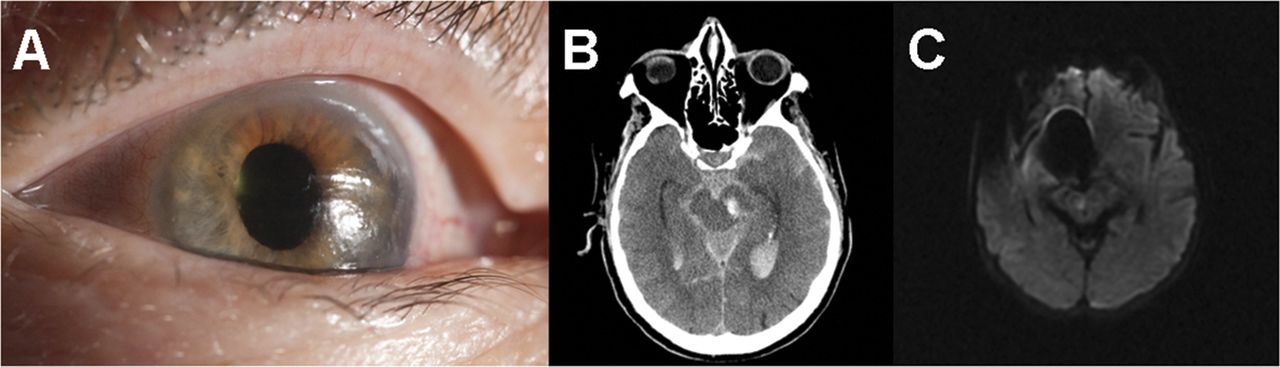

一个79岁的老人与一个无症状左颈动脉狭窄后立即进入昏迷左颈动脉支架。他有一个手术,圆的,7毫米,无反应的瞳孔,和一个椭圆形,6×5毫米,无反应的瞳孔(图,一个)。CT显示左侧中脑内急性出血花梗与蛛网膜下腔和脑室内出血(修改费舍尔规模4级)(图B)。接下来的一个小时里,他失去了所有脑干反射除了自主呼吸,持续了18个小时。他成为了脑死亡后,椭圆形配置呆了36个小时。

现年55岁的女性历史的神经内分泌癌肺转移的结肠癌被发现不省人事。她神经完好30分钟前被发现不省人事。在检查她是昏迷的瞳孔扩张,不反应的,椭圆形;有正确的外斜视。没有其他神经系统异常。CT血管造影的头部和颈部是模糊的。大脑的核磁共振显示病变hyperintense diffusion-weighted成像序列正确的靠近中央的中脑区域(图中,C),符合双边内侧丘脑核急性缺血性中风。